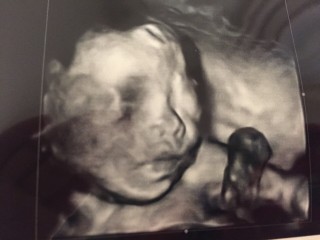

前の診断で8割女の子と言ってもらえましたが、今回は両足を持ち上げてて奥に入ってしまったため性別確定にはなりませんでした笑。 眼の上にへその緒がかかっているし、両足を持ち上げてて顔に膝がくっついてやんちゃな格好だけど、やっぱり4Dで見える我が子の顔はほんとうに愛おしい(^ω^)早く会いたいな~!

赤ちゃんは体重523gで週数からは順調に成長しているとのことでした。 初の3D写真で、口元に手を持って行って足を上げているのが分かります♪